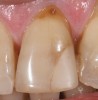

Most practitioners are currently taught to diagnose a D3 root-surface lesion (Figure 4) as active caries. The root surface is soft, sticky, cavitated, and may have debris that is easily removed with gentle palpation with the side of the explorer. Color changes may range from yellow orange/light brown to dark brown/black. The recommended treatment for D3 root-surface lesions includes remineralization of the root surface with products (pastes and varnishes) containing fluoride, calcium, and phosphate and subsequent restoration of the lost root-surface structure.

It is the experience of the authors that remineralization therapy applied to D3 root surfaces has the potential to result in root surfaces that, although discolored and cavitated, are completely hardened to a glassy, shiny surface. This allows the practitioner to preserve tooth structure that would otherwise be removed during preparation and provide a minimally invasive restoration. In cases where there is minimal cavitation in non-esthetic areas, the practitioner may opt to monitor the root surface for further change instead of placing a restoration. This classification system will aid the practitioner in diagnosing and monitoring these root surfaces.

Figure 4  This root surface is black and cavitated. When exploring with the side of the explorer, this root surface will feel soft and sticky, and it may be possible to remove soft debris from this lesion.

Figure 4